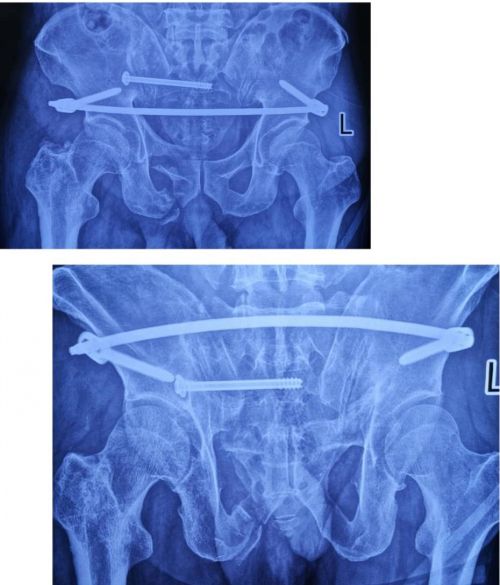

术后复查x线显示:骨盆骨折复位良好。

术后复查ct显示:骶髂螺钉固定位置良好。